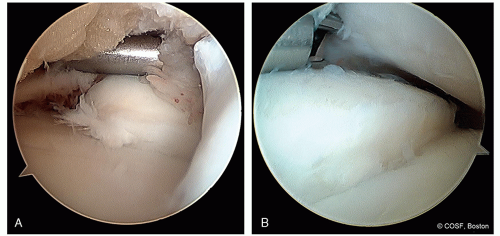

Arthroscopic Trans-Articular Drilling (Figure 34.12)

For stable lesions with intact overlying articular surface

Creates channels for revascularization

Can go transarticular or retrograde extra-articular

Technique

Goal: Penetrate lesion and pass through underlying subchondral bone

Probe the cartilage to identify the soft spot corresponding to the OCD lesion

Mark out the lesion with probe

Medial talar lesions

Arthroscope positioned through anterolateral portal

0.45 mm C-wires placed percutaneously, freehand

Start 1 cm proximal to standard anteromedial portal site, adjust as needed

Make sure C-wire stays medial to TA at all times

Aim for anterior portion of the medial talus OCD lesion

Plantar flex ankle

Determine if exposure is adequate

Drill to depth of approximately 2 cm

Place multiple drill holes several millimeters apart

Figure 34-12 ▪ A, Arthroscopic view from lateral portal of transarticular drilling of a medial talus osteochondritis dissecans (OCD) lesion. B, The ankle is held in plantarflexion to facilitate drilling of a posteromedial lesion. C, Intraoperative lateral fluoroscopic view showing arthroscopic transarticular drilling of a posteromedial OCD lesion. (Courtesy of Children’s Orthopaedic Surgery Foundation.)